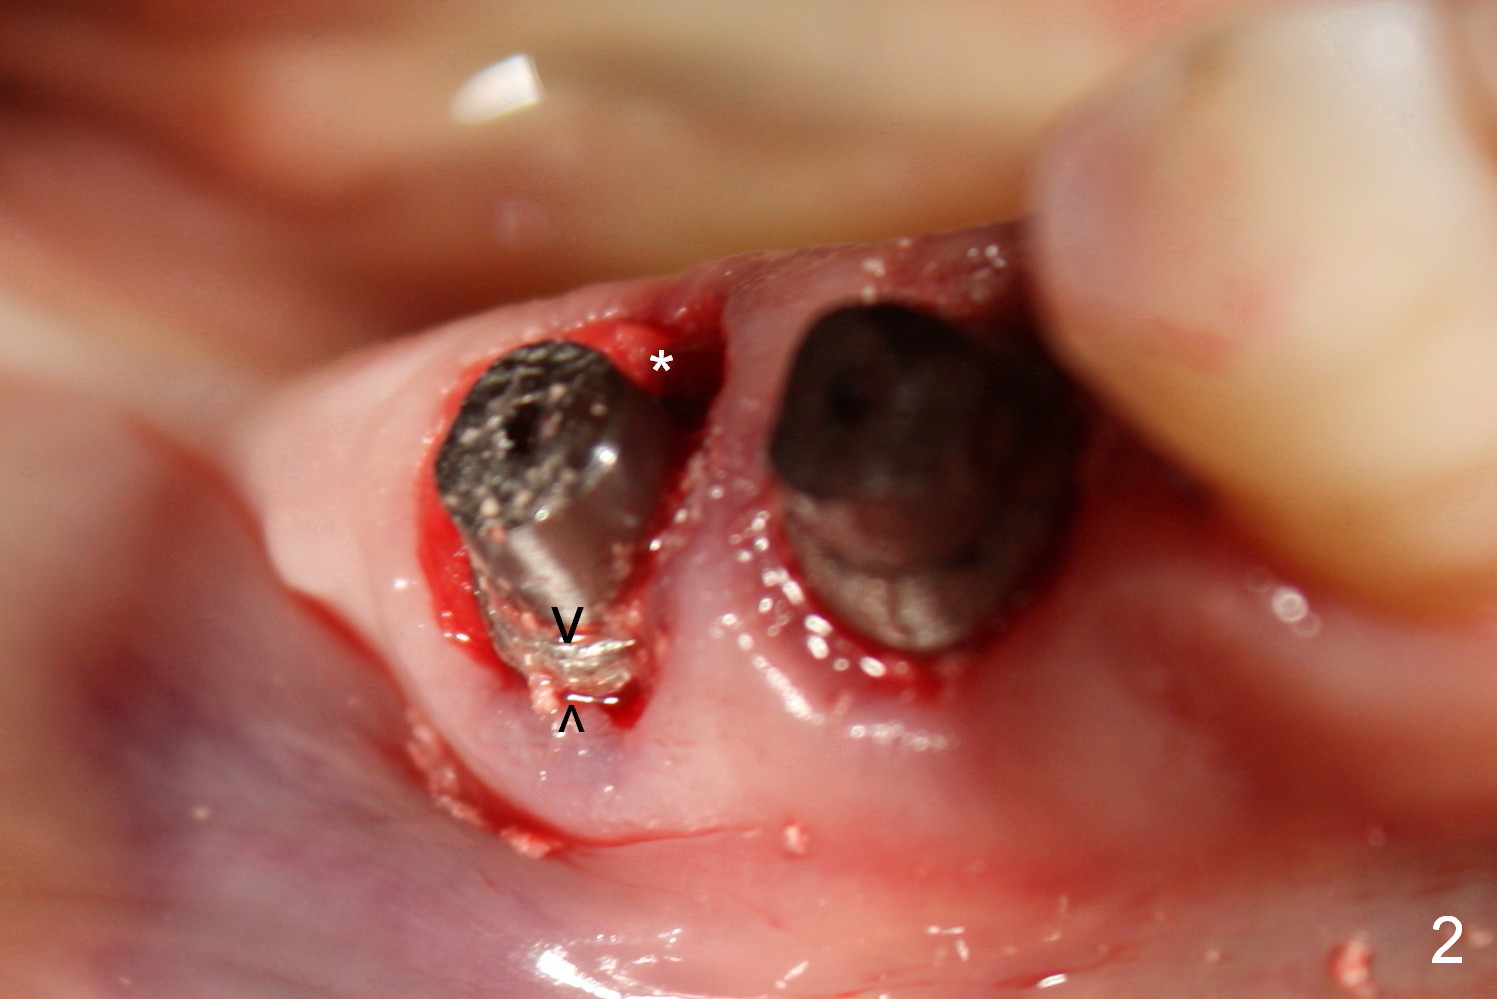

Fig.1 shows preop condition, whereas Fig.2 immediately post placement. In fact there is a space lingual to the implant of #29 (*). At that moment, the buccal margin is within normal limit (arrowheads). Ideally, the malpositioning can be corrected immediately. The implant should have been removed, repositioned and placed at the right position and trajectory. It is possible that attention was being paid to the depth of the osteotomies, because of proximity to the Mental Loop.